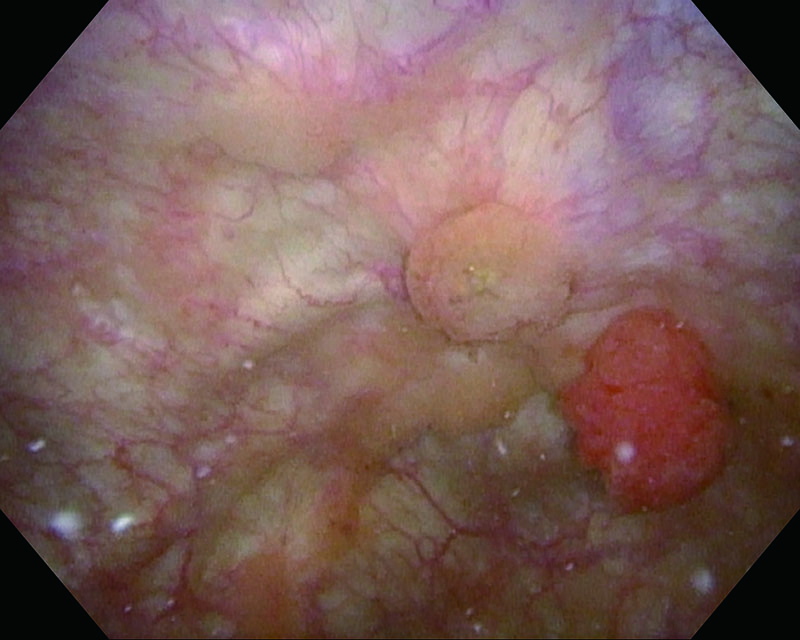

乳頭型・広基性 82歳・女性

通常光

NBI

病理 UC, pTa, High grade

コメント

NBIにて腫瘍辺縁が分かりやすくなると同時に、通常光では分かりにくい周囲の小さな娘腫瘍が確認できた。